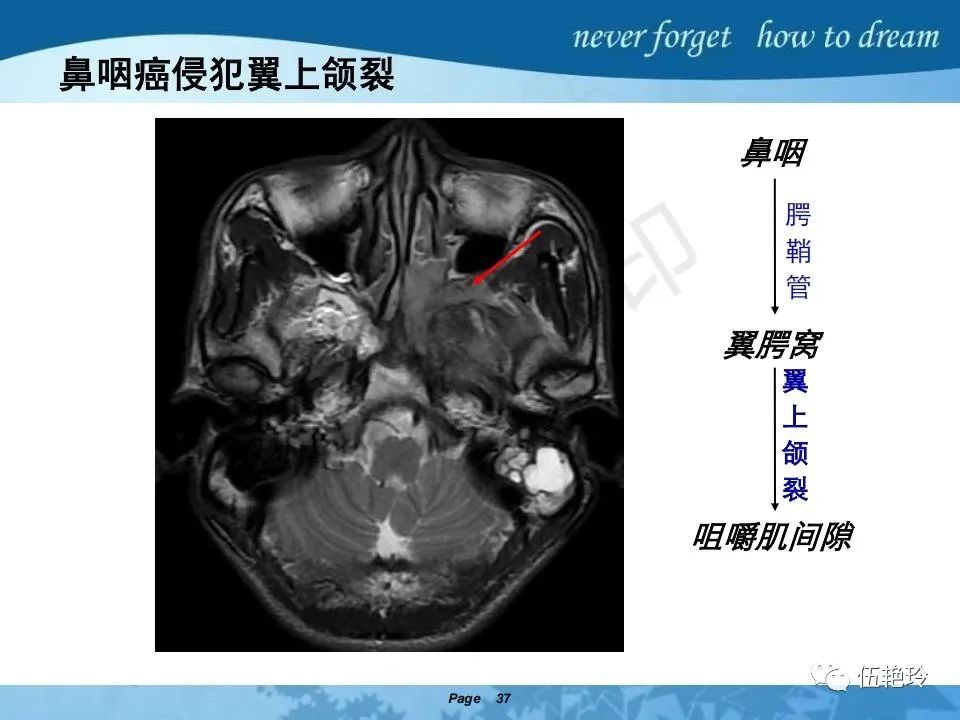

翼腭窝的解剖结构与鼻咽癌侵犯

颞下窝与咀嚼肌间隙

2.2 鼻咽特有的解剖途径:鼻咽癌原发灶循序进展的总途径:鼻腔(47.8%)→翼腭窝(15.2%)→ 眶下裂(3.2%)→眶尖(1.2%)→海绵窦(0.6%)。

2.31 向上颅内:①鼻咽顶壁→破裂孔(岩尖、斜坡)→蝶窦、海绵窦;②鼻咽顶壁→蝶骨基底部→蝶窦、海绵窦;③鼻咽侧壁→茎突前间隙→蝶骨大翼(卵圆孔)→海绵窦;④鼻咽侧壁→茎突前间隙→翼腭窝→ 颞下窝;⑤鼻咽前壁→鼻腔→翼突、翼腭窝→眶下裂→眶尖→海绵窦;⑥鼻咽前壁→鼻腔→上颌窦、筛窦;